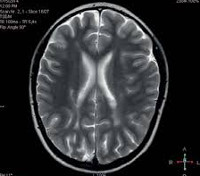

• МРТ головного мозга Используется метод FLAIR (подавление сигнала свободной воды). Отмечены атрофические, кистозно-глиотические деформации. Области лейкоарайоза характеризуются тем, как пропитывается белое вещество, и очаговыми корковыми воспалительными изменениями.